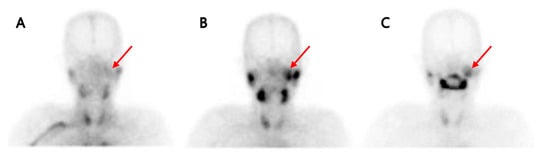

Background: The purpose of this study was to examine the relationship between qualitative characteristics and quantitative parameters from contrast-enhanced ultrasound (CEUS) and microvessel density (MVD) in hepatoblastoma (HB), as well as to investi...